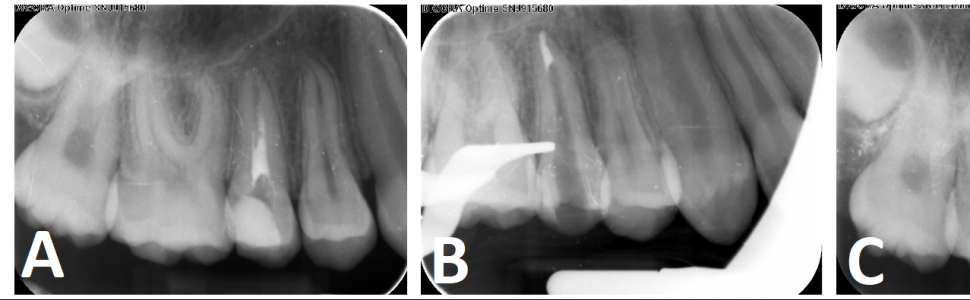

Ryc. 2. Ząb 15 leczony endodontycznie (otwór wierzchołkowy o rozmiarze 100): A. zdjęcie rentgenowskie wykonane w trakcie leczenia, w kanale widoczny materiał zawierający jodoform; B. zdjęcie rentgenowskie wykonane po wypełnieniu części wierzchołkowej preparatem Well-Root PT; C. zdjęcie rentgenowskie po wypełnieniu części środkowej i koronowej kanału.